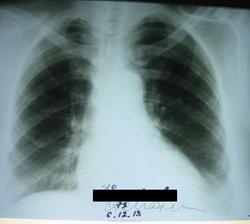

качество не очень, но может будут мнения ) Заранее спасибо

мой коллега описал, я спросила, сказал сосуды, но я не согласна, притащила на сайт

В данном случае - ДА! есть ОЧАГИ! в плащевых зонах - это 100пудово патология. Вопрос : влияет ли ЭТо на жизнь пациента? Не фиброз ли очаговый? (или в шахте 3-4 очага заработал?) Если уж выставили снимки - не затруднитесь и АРХИВ выставить ( или он первый раз в жизни снимок сделал?), тогда и всем счастье будет.Динамику!

Не сосуды... Бока в принципе нет, или нет здесь?))

Как по мне сосуды.

посмотрела флюшку, но только полгода назад, да есть очаги, смотрятся как плотные